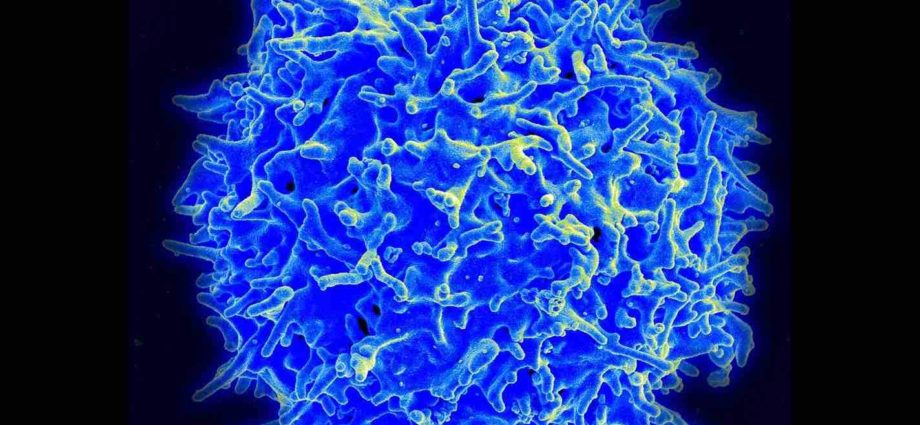

Le corps des êtres vivants tels que des animaux et des hommes possède une incroyable quantité de cellules, environ 100 000 milliards au total. Par conséquent, il est en état de renouvellement cellulaire permanent, à partir de la naissance jusqu’à la mort. Il est en quelque sorte constamment remis à neuf.

Pratiquement tous les organes, tous les tissus et toutes les cellules sont soumis à ce renouvellement cellulaire permanent et vont être complètement régénérés plusieurs fois dans une vie, à une fréquence plus ou moins élevée en fonction des cellules. Ce qui fait qu’au bout du compte, l’immense majorité des cellules et des organes sont plus jeunes que l’individu lui-même.

Ce vaste écosystème cellulaire – qui est finalement notre organisme – contient environ 250 types de cellules différentes. La grande majorité est soumise au renouvellement cellulaire, sauf quelques exceptions, comme, par exemple, les neurones et les cellules cardiaques où le renouvellement est très lent ou quasi inexistant.